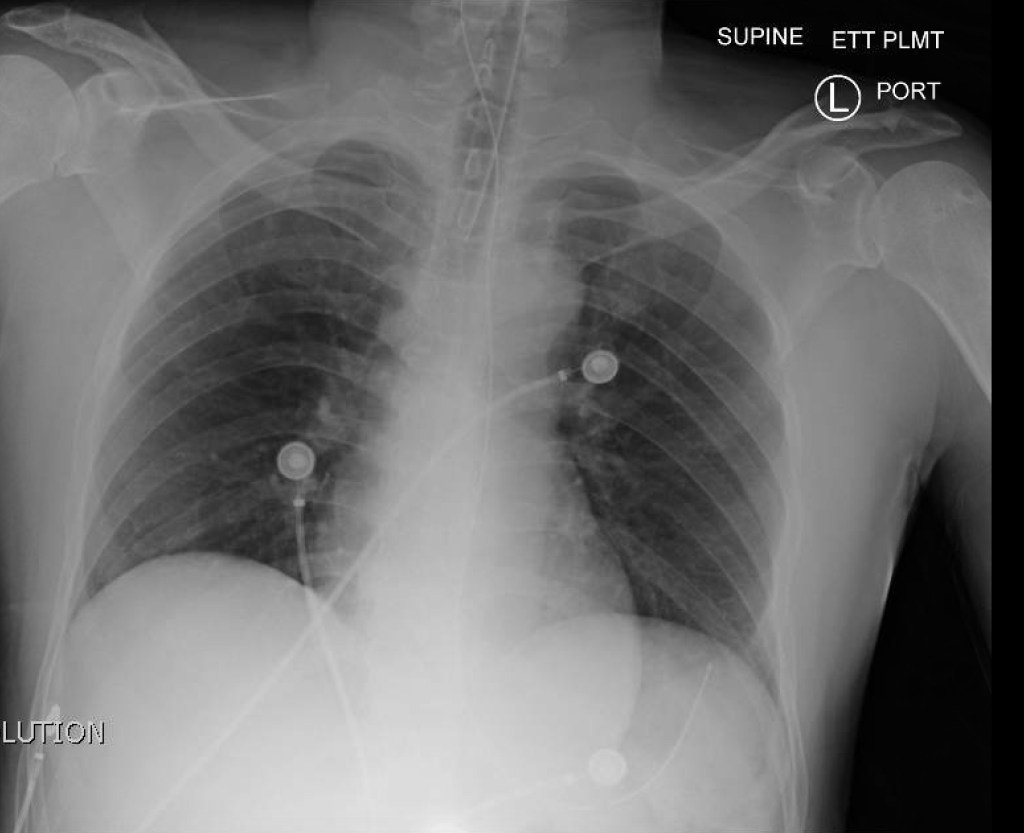

A 24-year-old previously healthy male presents to the ED with absent vital signs. He is out for a trail run when he becomes trapped in waist deep cold water. When he is found by search and rescue, he is awake with altered mental status. He has a cardiac arrest on retrieval and is found to be severely hypothermic. CPR and ACLS is initiated and he is transferred to the nearest community ED. The resuscitation team is expected to perform ACLS specific to hypothermic arrest. The patient will require intubation, active rewarming, defibrillation and discussion with the ECMO physician on call for transport and ECMO assisted rewarming.